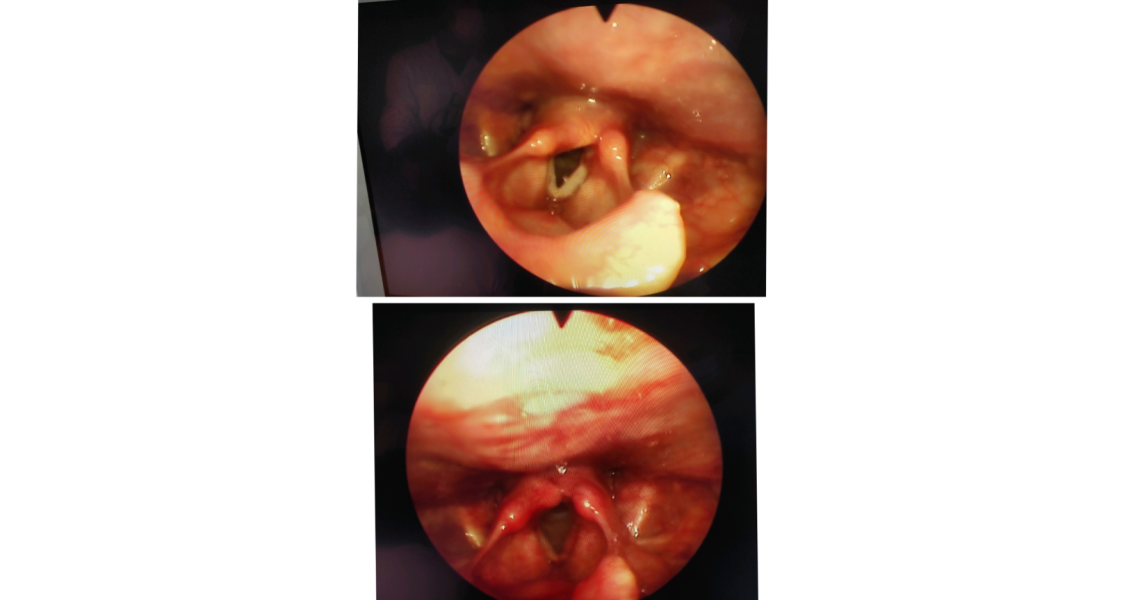

В отоларингологічному відділенні КП «2-а МКЛ ПМР», де знаходиться клінічна база кафедри оториноларингології з офтальмологією, відбувся майстер-клас з ендоскопічного ендоларингеального видалення новоутворень гортані для лікарів-інтернів І та ІІ років навчання. Провів майстер-клас д.мед.н., професор кафедри Юрій Гасюк. Таке малоінвазивне оперативне втручання є сучасним методом оперативного лікування новоутворень порожнини гортаноглотки та гортані, що дозволяє мінімізувати ризики розвитку можливих ускладнень, а також пришвидчити реабілітацію хворого в післяопераційному періоді.

На початку майстер-класу професор Юрій Гасюк розглянув з лікарями-інтернами особливості клінічної анатомії та фізіології гортані, ознайомив з основними етапами підготовки технічного оснащення та алгоритмом ендовідеоскопічного огляду гортані, продемонстрував учасникам проведення даної методики. Під час практичної частини майстер-класу молоді лікарі мали змогу під контролем досвідченого викладача відпрацювати навички та отримати необхідні консультації. Наприкінці майстер-класу професор Юрій Гасюк розглянув типові помилки, що виникали при виконанні даної маніпуляції, та відповів на запитання лікарів-інтернів.